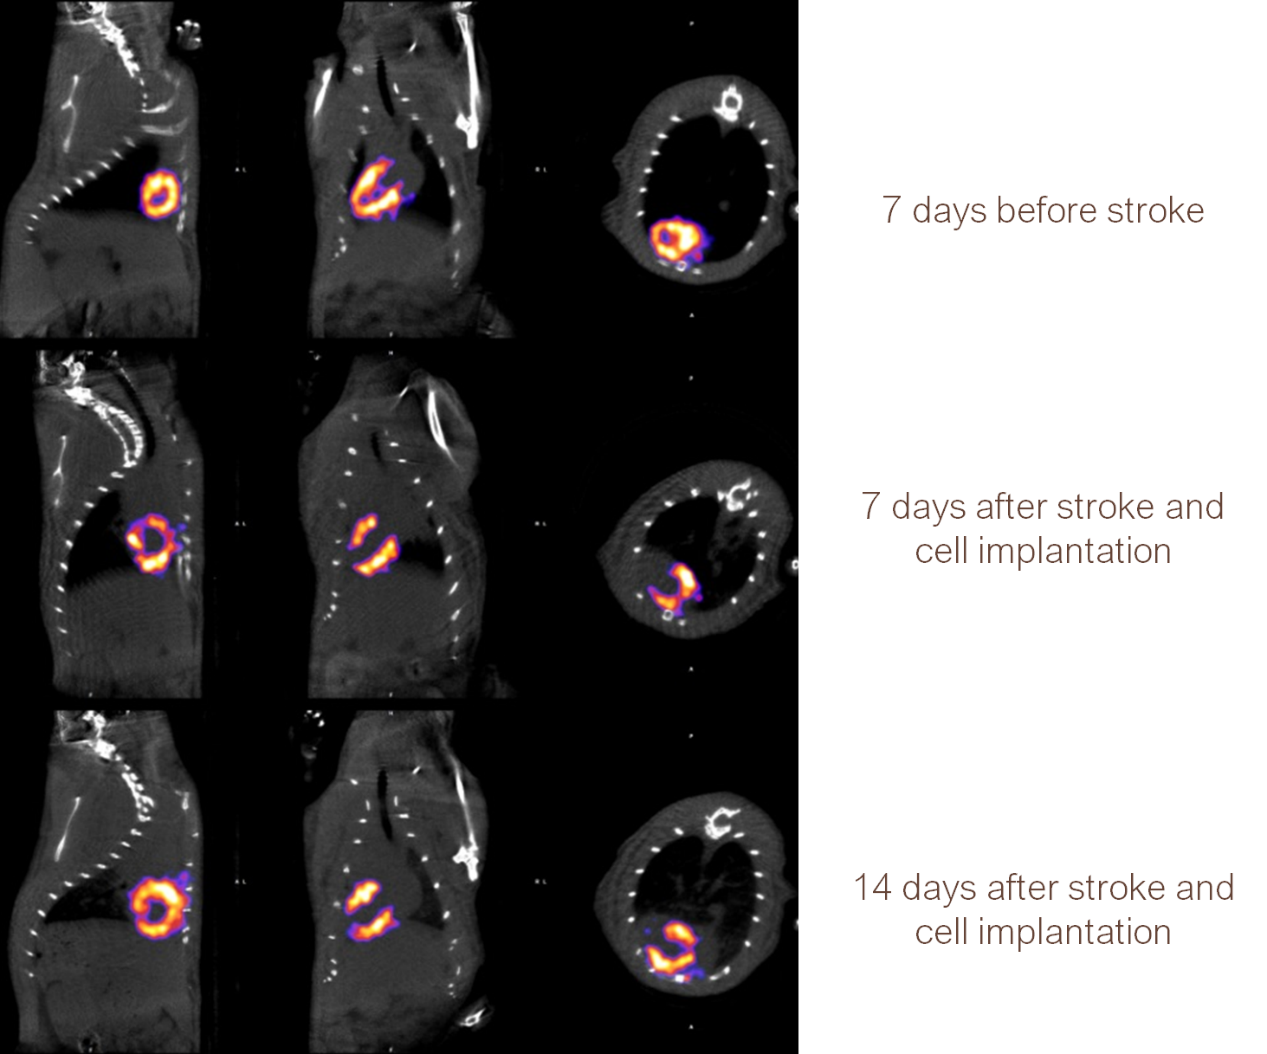

2、心血管SPECT成像

小鼠心肌SPECT成像:药物99mTc-MIBI反映注药当时情况下的心肌血流灌注量,63.27 MBq (1.71 mCi) @ start acquisition,采集时间40min。

大鼠心血管中风模型,中风前后及用药后,观察心脏血流状态。